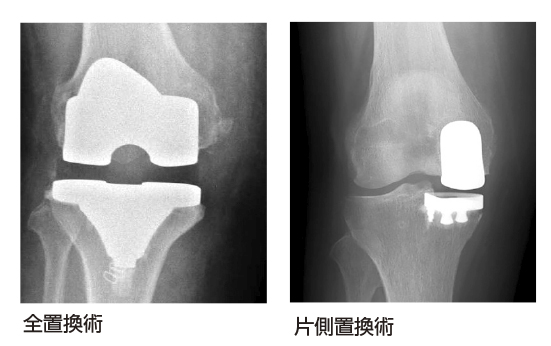

人工膝関節置換術

人工膝関節置換術は変形性膝関節症末期の高齢者に対して行う手術で、高齢者の増加と医療技術の進歩により、日本だけで年間8万件以上も行われています。大腿骨・脛骨の軟骨が摩耗・欠損し、軟骨下骨が露出してガタガタになった関節表面(荷重部)を削って、新しい人工の関節に置換する手術です。関節全部を置き換える全置換術と、関節の一部を置き換える片側置換術があります。